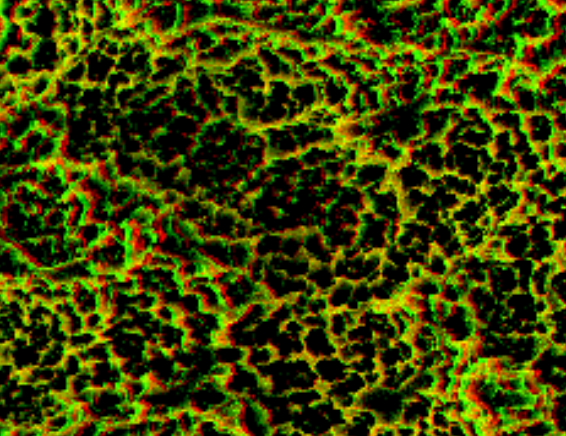

Intimate contact between extracellular matrix produced by Osteoblasts, and the Titanium oxide surface (100 Å)

1 Å = one ten-billionth of a meter

Increased oxide thickness with time (5- 200 micrometer)